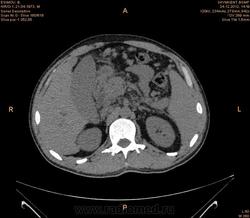

Предварительно образование головки ПЖ, и в печени. Что с ферментами?

на операций рак головки подж.железы с метастазир. печень.

инфильтрация тут нисходящей 12 перст кишки , расширенного холедох,расширенный вирсунгов проток ,нижная граница очень близко прилежит к нижней полой вене с правой почечной веной ,но четко визуализирутся передний листок фасции Героты(нельзя исключить ее инфильтрацию), инфильтрация конгломератом увеличенных лимфатических узлов ворот печени портальной вены с варикозным расширением вен, на вышележащий срезах четко определяются верхняя брыжеечная вена и артерия ,не хватает срезов для полной визуализации(помогли бы мпр),инфильтрирована восходящая ободочная кишка,конгломерат лимфат узлов за головкой поджелудочной железы в виде гиподенсивного участка вытянутой формы , ,мтс в печень,парааортальные